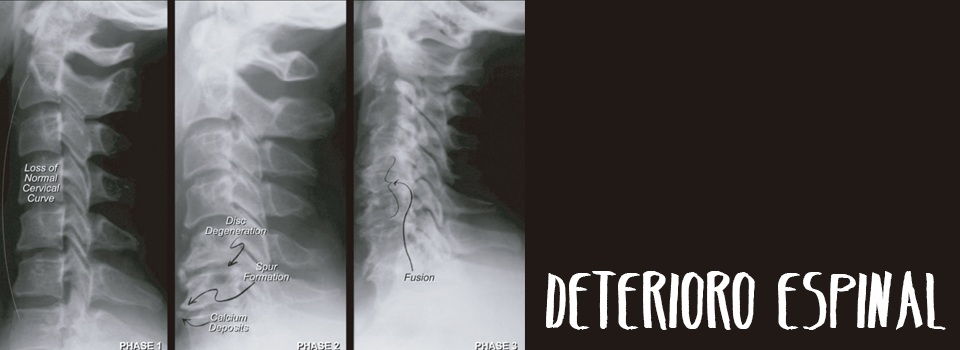

Deterioro espinal

Como otras articulaciones que soportan peso, como ser la cadera, rodilla y tobillo, el deterioro ocurre cuando las articulaciones de desalinean y se dañan en función.

Con el tiempo el mecanismo incorrecto de las articulaciones espinales desaliñadas puede llevar a hernias de disco, artrosis y deterioro de la columna.

Las radiografías muestran el desarrollo de artrosis ósea en los bordes de las vértebras y debajo de los discos.

Eventualmente las vértebras se fusionan. El deterioro espinal es un proceso de envejecimiento prematuro que puede prevenirse con la mecánica espinal apropiada y la alineación.